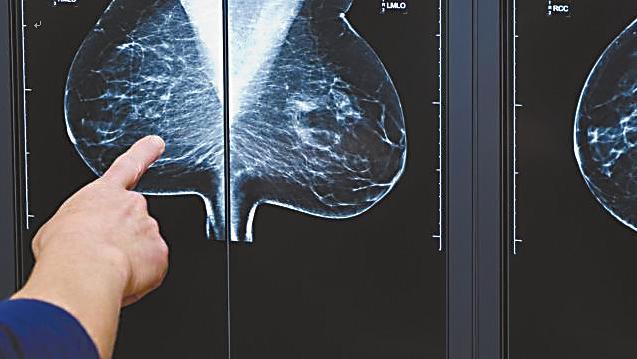

四、乳腺癌

乳腺癌是我国女性最常见的恶性肿瘤。一般风险人群影像筛查起始年龄为40岁,高危女性需提前。其中,携带高外显率有害突变基因的健康女性,筛查起始年龄应提前至25岁。

1.重点筛查项目:乳腺X线摄影、乳腺超声、乳腺核磁检查

![]()

乳腺X线摄影

3.定期筛查时间:

通常建议一般风险人群40岁开始筛查。乳腺癌高危人群建议从25岁起,每年进行一次乳腺超声或钼靶检查,必要时联合增强MRI,持续至75岁或预期寿命不足5年。携带高外显率有害突变基因的健康女性,筛查起始年龄提前至25岁。